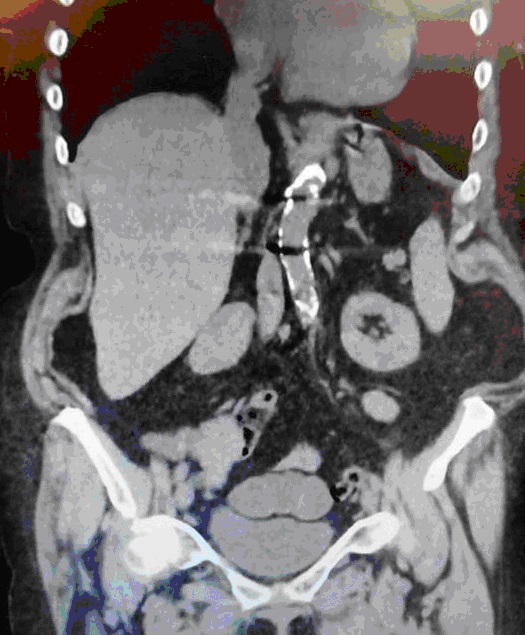

Riedel’s lobe of the liver

We report the case of an 80-year-old woman, presented to our department for an Intestinal obstruction due to postoperative adhesions from an anterior exploratory laparotomy. Preoperative imaging showed a downward elongation of the liver, ending at the level of the iliac crest. Originally reported in 1888 by a German Surgeon named Carl Ludwig Riedel in seven female patients who had palpable masses, they were all confirmed by surgical exploration. The potential complications are rare and include torsion, mass effect morbidity and laparoscopic associated difficulty during different surgical procedures. Unnecessary imaging can be avoided with the knowledge of this normal variant of the right lobe of the liver.